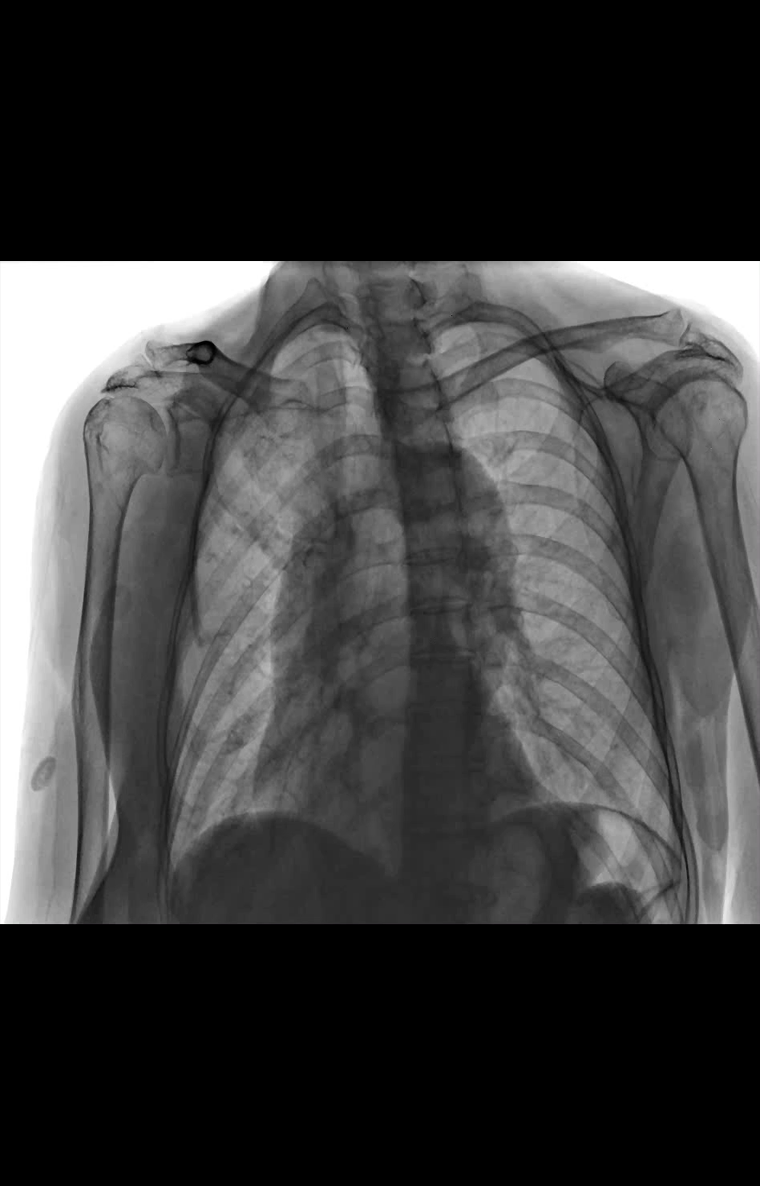

高清動態平板探測器

搭載自主研發超清大視野動態平板探測器,600微米碘化銫大幅提升X線轉化效率,獨特的非晶硅陣列與高速讀取集成電路緊密協作,輕松實現多幀率透視與高清點片。

17x17英寸

大幅面成像 -

900萬

高清像素點片 -

線性探測平面

圖像無畸變、無失真

專業的影像處理系統

“騰靈”系列搭載的IEAE影像處理系統,具備多項發明專利。本系統采用多頻域圖像處理技術,其6大核心處理模塊使影像具有優秀的一致性、柔和性、空間層次感和紋理細膩度,為用戶精準診斷病灶奠定了堅實的基礎。